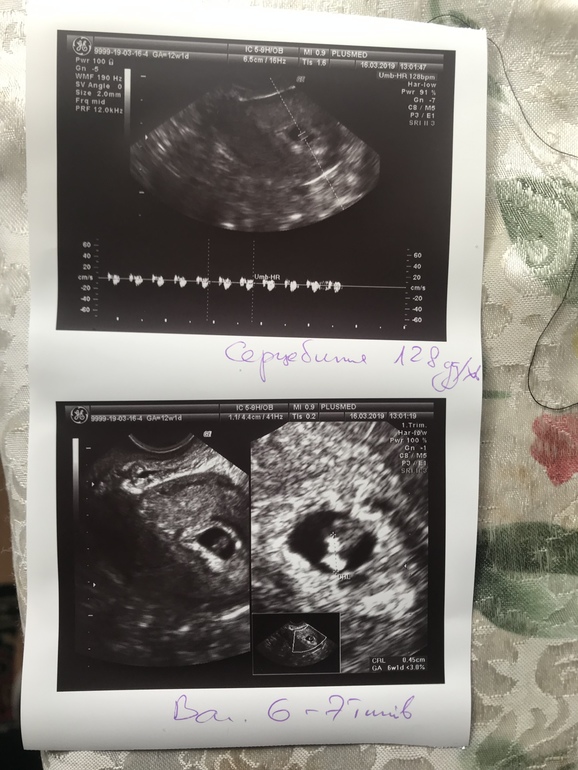

Замершая и внематочная беременностьПривет, девочки! Были мы сегодня на УЗИ по причине коричневых выделений, на передней стенке матки есть достаточно большая гематома, врач сказала, что будет выходить, плод на задней стенке матки. После УЗИ сейчас опять началась алая кровь и очень болит живот, как на месячные (((( лежу, лекарства приняла. О плоде по УЗИ: СБ 128 уд/мин, КТР-0,45 см, срок 6-7 недель (эмбриональных 5 и 3). У меня вопрос-не очень ли маленький размер плода, если брать соотношение с неделями, учитывая то, что мой ХГЧ на 29 ДПП был 4216? Фото добавляю.